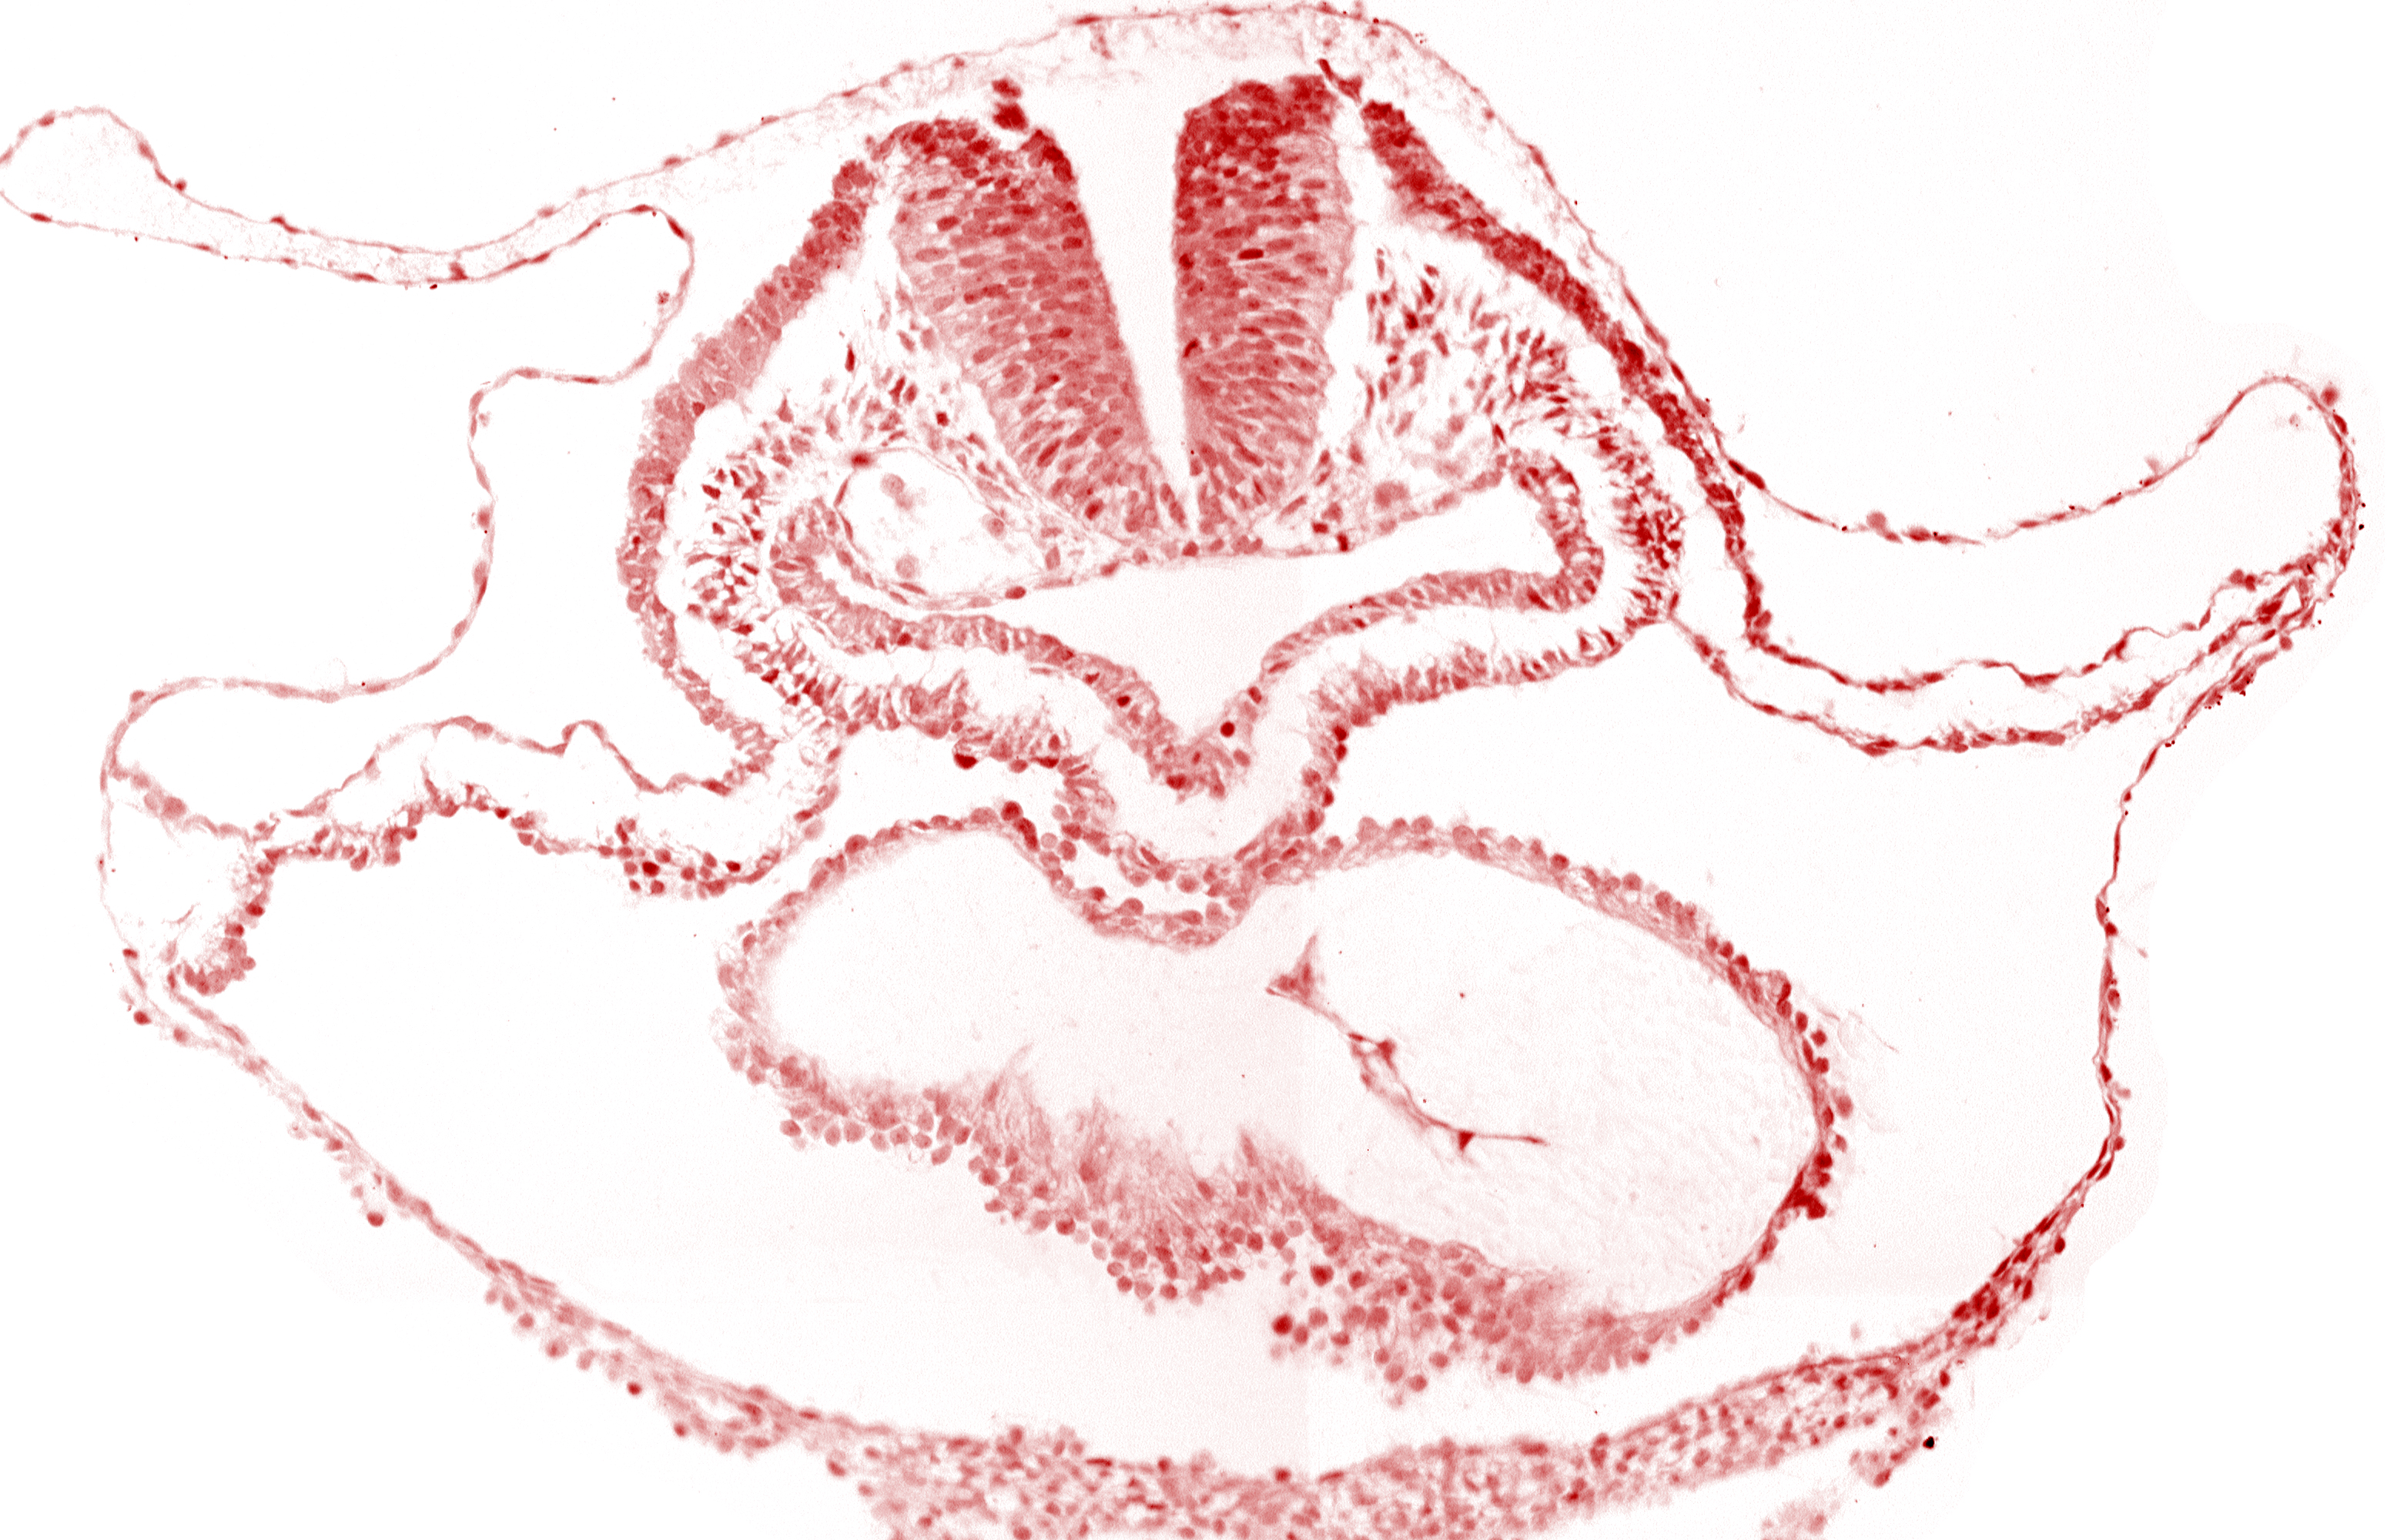

Carnegie Embryo #6330 | Location: 01-07-08

Keywords: cephalic edge of otic placode, lateral pharyngeal recess, neural fold [rhombencephalon (Rh. B)], pericardial cavity, pericardial sac, presumptive left ventricle

Source: The Virtual Human Embryo.